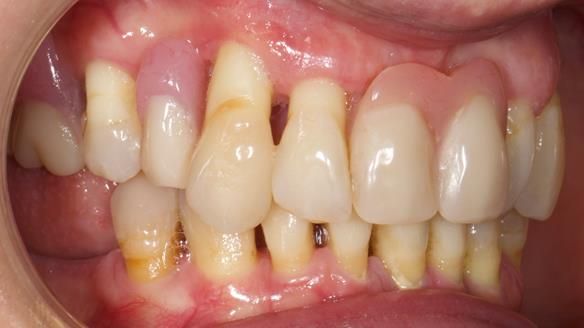

She had previously suffered from generalised periodontitis – stage IV, grade C, currently stable, with reduced attachment across the upper arch.

By the time she came to me, her periodontal condition was stable — but the aesthetics in the upper jaw were very poor.

Dr Syed Abad — my colleague and a Specialist in Periodontics — had successfully stabilised her gum health.

We provided her with an immediate upper denture (Mk 1), followed by a definitive metal-based upper denture (Mk 2). A lower removable partial denture was discussed, to be made only if needed once the upper treatment was complete. However, at review, this wasn’t necessary — Adnana had excellent neuromuscular control and function, even with a shortened dental arch (SDA).